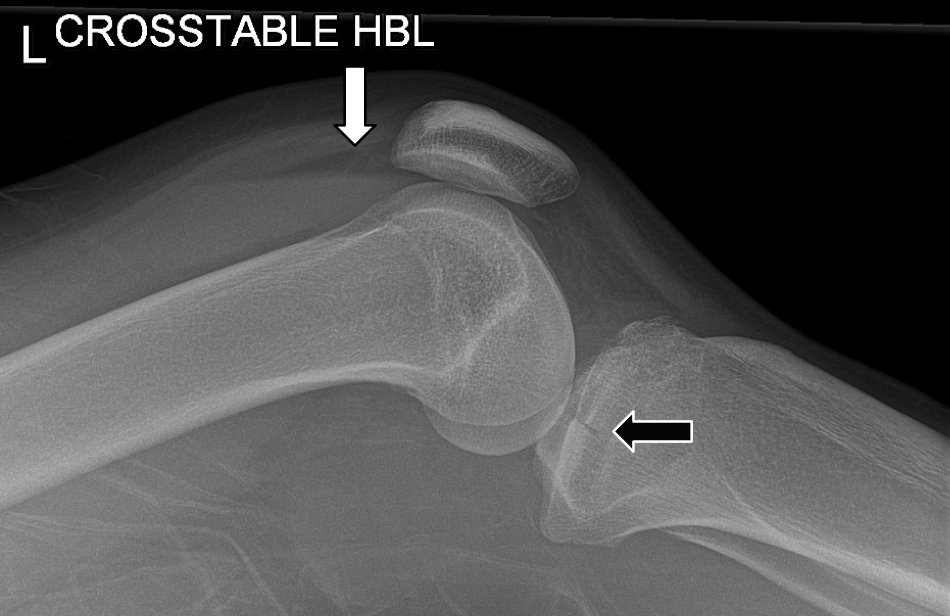

Describe the appearance of lipohaemarthrosis on x-ray

You will notice that there is a very straight line (arrow) at the superior aspect of the fluid, above which there is some low density material. This is fat floating on blood, and makes this a lipohaemarthrosis. The reason this is significant is that it means that there must be an underlying fracture, even if one cannot be seen on the radiograph (because the fat is actually marrow fat, and must have leaked into the joint through a fracture).